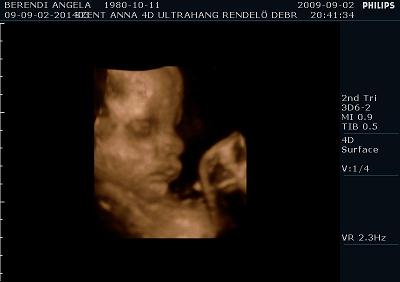

Ma voltunk UH-on. És a méretei alapján még mindig egy héttel idősebbnek nézik, de súlya tök normális 2350 gramm. Szóval azt mondják nem lesz akkora mint a kis Levi manó volt. Ennek azért örülök mert nagyobb az esély hogy meg tudom szülni, mivel nekem az első császár volt. Szóval drukkoljatok lányok!!